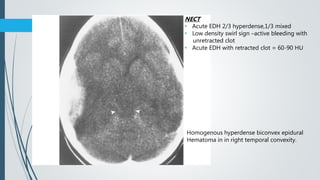

Homogenous hyperdense biconvex epidural

Hematoma in in right temporal convexity.

NECT

• Acute EDH 2/3 hyperdense,1/3 mixed

• Low density swirl sign –active bleeding with

unretracted clot

• Acute EDH with retracted clot = 60-90 HU